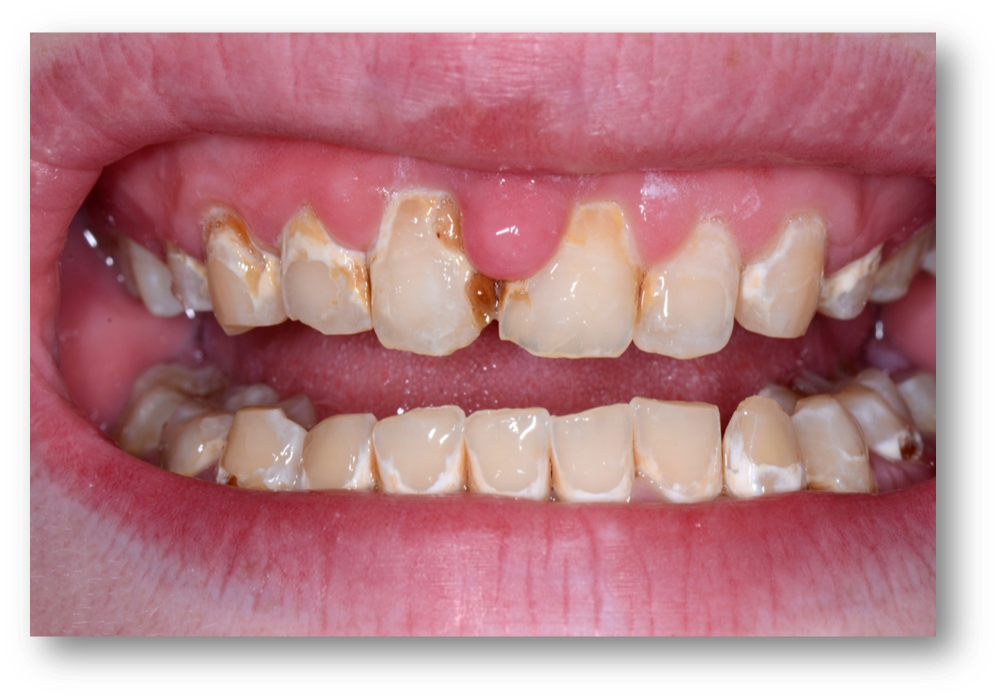

Example 1: Soft-Tissue Recontouring and Esthetics

The first example is of a mouth that needed soft-tissue recontouring with better esthetics (Figure 1). A diode laser is important for debridement, soft-tissue engineering, and better cleaning afterwards. The diode laser is popular in dentistry due to its small size and ease of use for minor soft-tissue surgery.1 It is a minimally invasive technology that offers advantages superior to those of the conventional scalpel, such as reduction of bleeding and inflammation and the lower probability of scars.2 Its effectiveness is comparable with that of other types of lasers, and it is an option of lower cost and greater ease of use.  Based on its photothermal effect, the diode laser is used for the removal of small lesions of the oral mucosa by excision or vaporization procedures.3

Fig 1. A patient was in need of soft-tissue recontouring and better esthetics.

Figure 1